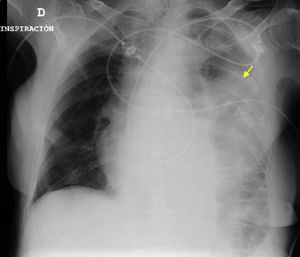

An 85-year-old woman was seen in the emergency room with dizziness following a traffic accident. After a few hours she developed breathing difficulties, desaturation and the absence of vesicular murmur upon auscultation. Pulmonary ultrasound evidenced a “C pattern” in the left hemithorax, with peristaltic motion (Fig. 1), and the chest radiographs (Fig. 2) and thoracoabdominal computed tomography scan (Fig. 3) confirmed the diagnosis of diaphragmatic rupture with bowel loop herniation towards the left thoracic space. Emergency surgical repair was carried out and the patient was discharged from intensive care after 5 days. Diaphragmatic rupture often proves fatal – hence the importance of tools allowing early diagnosis and treatment, since they condition the prognosis in such cases.